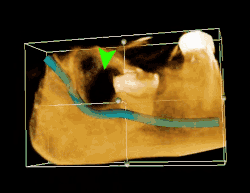

| 3D CT of an impacted wisdom tooth adjacent the inferior alveolar nerve prior to removal of wisdom tooth | |

Coronectomy is a procedure where the crown of the impacted wisdom tooth is removed, but the roots are intentionally left in place. It is indicated when there is no disease of the dental pulp or infection around the crown of the tooth, and there is a high risk of inferior alveolar nerve injury.[32]

Coronectomy, while lessening the immediate risk to the inferior alveolar nerve function has its own complication rates and can result in repeated surgeries. Between 2.3% and 38.3% of roots loosen during the procedure and need to be removed and up to 4.9% of cases require reoperation due to persistent pain, root exposure or persistent infection. The roots have also been reported to migrate in 13.2% to 85.9% of cases.[32]